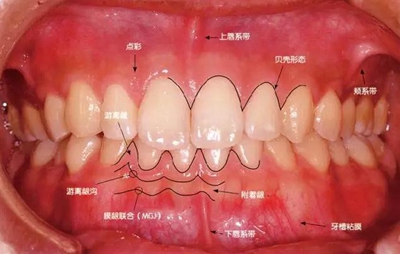

健康、正常的牙周組織是什么樣的臨床表現(xiàn)?

健康牙周組織的牙齦邊緣呈珊瑚粉,邊緣牙齦略呈圓弧狀。牙間可見三角形的牙間乳頭,牙齦邊緣相連呈貝殼形。

附著齦與游離齦相連時(shí),有時(shí)有游離齦溝存在(成人的30~40%)。

附著齦通過(guò)膠原纖維牢固結(jié)合骨骼與牙骨質(zhì),因此可見不可動(dòng)、硬而緊繃的點(diǎn)彩(橘皮樣點(diǎn)狀凹凸)。

從牙齦牙槽粘膜到根尖有牙槽粘膜。牙槽粘膜為暗紅色,與骨骼結(jié)合較松,故可動(dòng)。

健康且正常的牙周組織臨床圖像